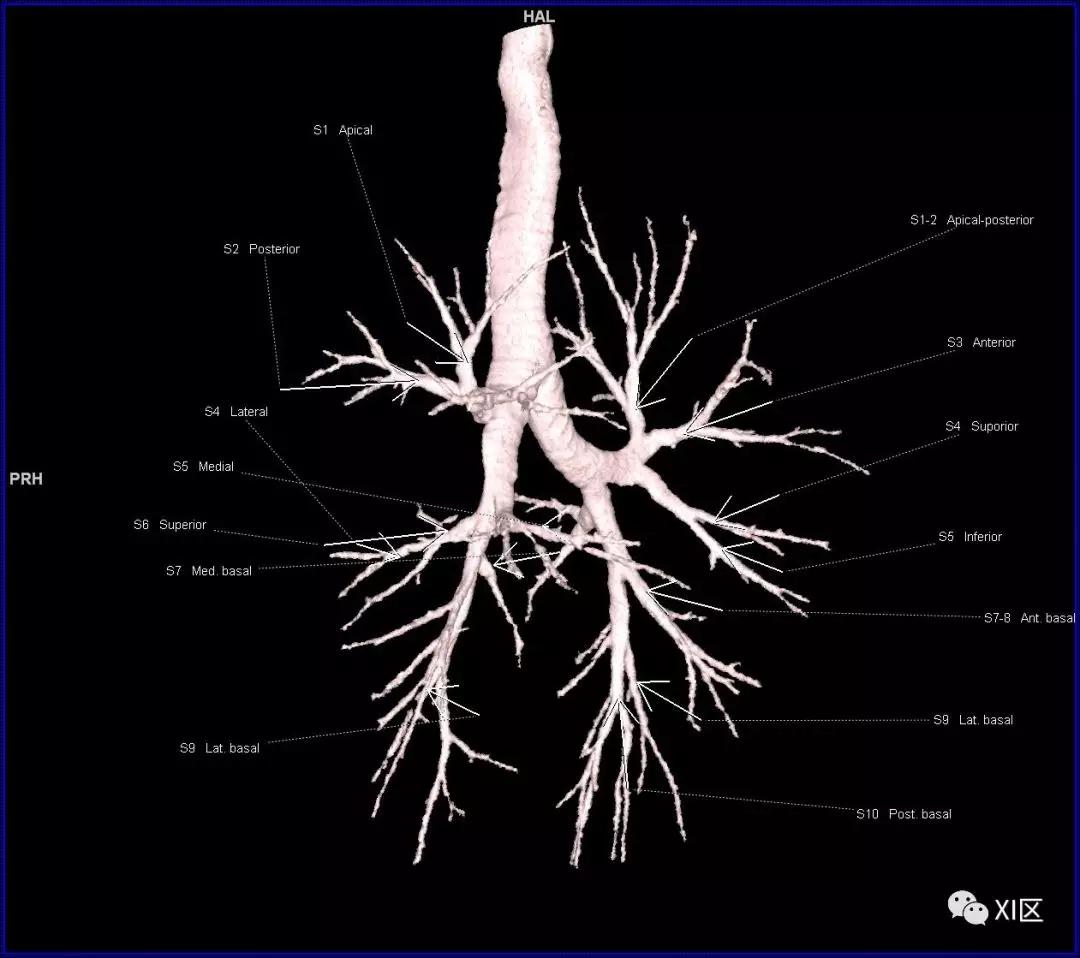

气管树的解剖

人的支气管(第1级)至肺泡约有24级分支。支气管经肺门入肺,分为叶支气管(第2级),右肺3支,左肺2支。叶支气管分为段支气管(第3~4级),左肺8支、右肺10支。段支气管就是肺的分段的依据。段支气管反复分支为小支气管(第5~10级),继而再分支为细支气管(第11~13级),细支气管又分支为终末细支气管(第14~16级)。从叶支气管至终末细支气管为肺内的导气部。终末细支气管以下的分支为肺的呼吸部,包括呼吸细支气管(第17~19级)、肺泡管(第20~22级)、肺泡囊(第23级)和肺泡(第24级)。

气管支气管形如树状,因此也称气管支气管树。

段支气管的命名(图片源自网络)

段支气管的命名